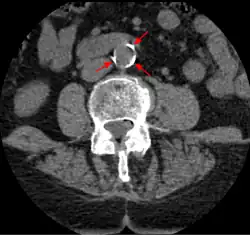

The calcification deposits,[74] after they have become sufficiently advanced, are partially visible on coronary artery computed tomography or electron beam tomography (EBT) as rings of increased radiographic density, forming halos around the outer edges of the atheromatous plaques, within the artery wall. On CT, >130 units on the Hounsfield scale (some argue for 90 units) has been the radiographic density usually accepted as clearly representing tissue calcification within arteries. These deposits demonstrate unequivocal evidence of the disease, relatively advanced, even though the lumen of the artery is often still normal by angiography.

Examples of anatomical detection methods include coronary calcium scoring by CT, carotid IMT (intimal media thickness) measurement by ultrasound, and intravascular imaging techniques, such as intravascular ultrasound (IVUS), and intravascular optical coherence tomography (OCT),[85][86] allowing direct visualization of atherosclerotic plaques.